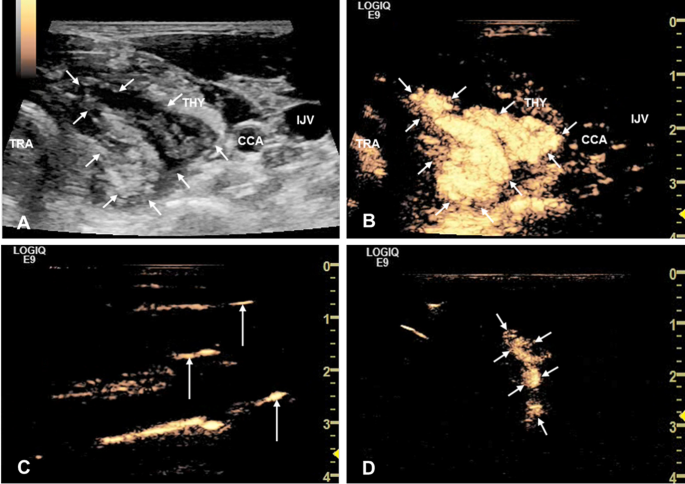

Figure 2 shows the process of absorption of the isolating fluid containing contrast agent by the perithyroid lymphatic vessels.

The absorption of the isolating fluid through perithyroid lymphatic vessels. (A) On B-mode US, the pretracheal space (short arrows) between the trachea and the lateral lobe of thyroid showed a triangular anechoic region. (B) On CEUS, the pretracheal space (short arrows) was perfused by contrast agent, displaying as hyperperfusion area. (C) On CEUS, the enhanced perithyroid lymphatic vessels (long arrows) displayed as liner structures, which demonstrated that the contrast agent, as well as the isolating fluid was absorbed through lymphatic system. (D) Thirty minutes later, the range of hydrodisection area in pretracheal space (short arrows) became smaller. THY = thyroid; TRA = trachea; CCA = common carotid artery; IJV = internal jugular vein; US = ultrasound; CEUS = contrast-enhanced ultrasound.

Post-ablation, the absorption of isolating fluid through the lymphatic system was closely observed within a 60-minute timeframe (Fig. 2).